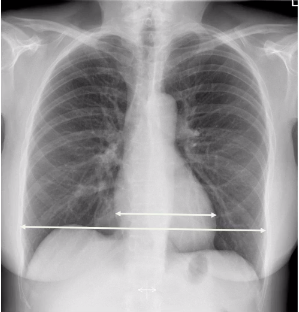

what is a cardiomegaly?

whats wrong here?

blunted cardiophrenic and costophrenic angles